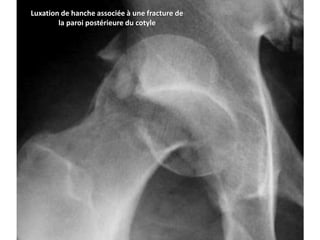

Une place particulière est à donner aux fractures de

l’acétabulum que l’on rencontre dans 20 % des luxations

postérieures (Fig. 4), et aux fractures de la tête fémorale qui

représentent 13 % des cas.

Luxation de hanche associée à une fracture de

la paroi postérieure du cotyle

Luxation de hancheassociée à une fracture de la paroi postérieure du cotyle